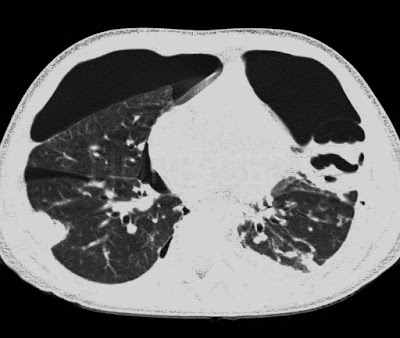

TC mostra pneumotórax bilateral e nódulos escavados